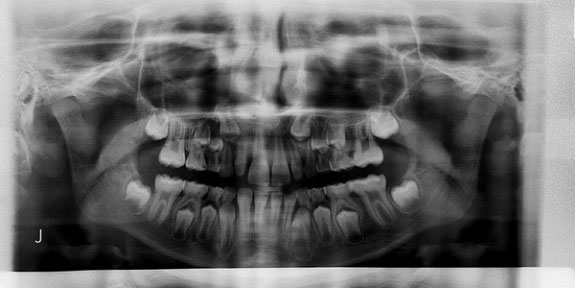

Röntgendiagnosztika